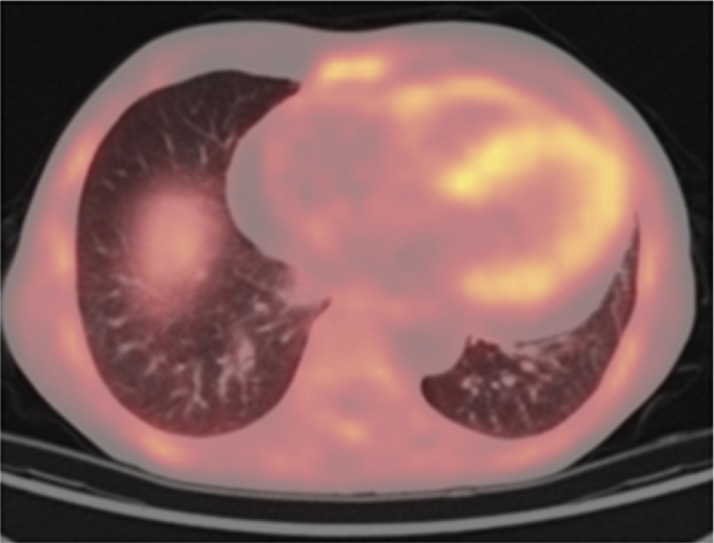

Abstract Image